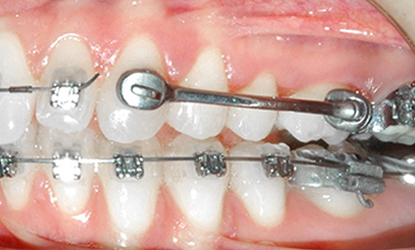

>   Jednostronne użycie Dystalizera Carriere w przypadku zaburzonych triad (wzajemne kontakty zębów górnych i dolnych) zabezpieczenie wyników leczenia miniimplantem ortodontycznym.